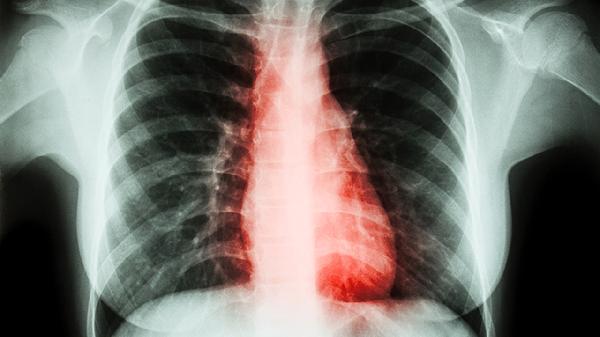

Lung-RADS4B类肺结节是指肺部影像学检查中高度可疑恶性的结节,需进一步临床干预。Lung-RADS是美国放射学会提出的肺结节分类系统,4B类结节恶性概率较高,通常表现为直径超过8毫米的实性结节或部分实性结节,伴有分叶、毛刺等可疑征象。

Lung-RADS4B类结节的影像特征包括结节边缘不规则、生长速度异常或伴随胸膜牵拉等。这类结节可能由原发性肺癌、转移性肿瘤或罕见感染性疾病引起。临床处理需结合增强CT、PET-CT或穿刺活检明确性质,部分患者需短期复查监测变化。对于持续存在的4B类结节,胸腔镜手术切除是常见干预手段。